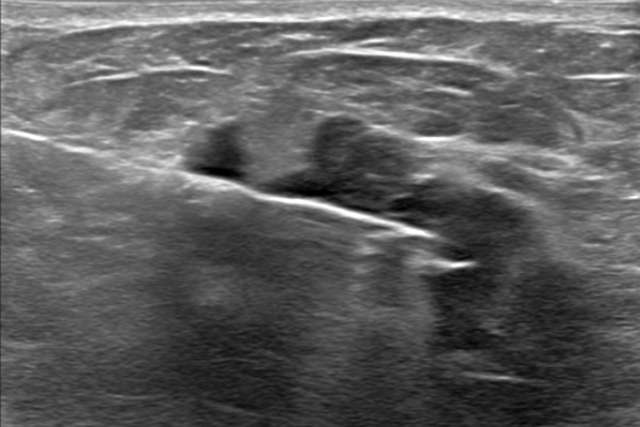

Cases

Delve into cases developed by our section to uncover key clinical presentations and image findings that can help guide your practice.

Breast Tissue

Pathology

From localizing to characterizing suspicious tissue.